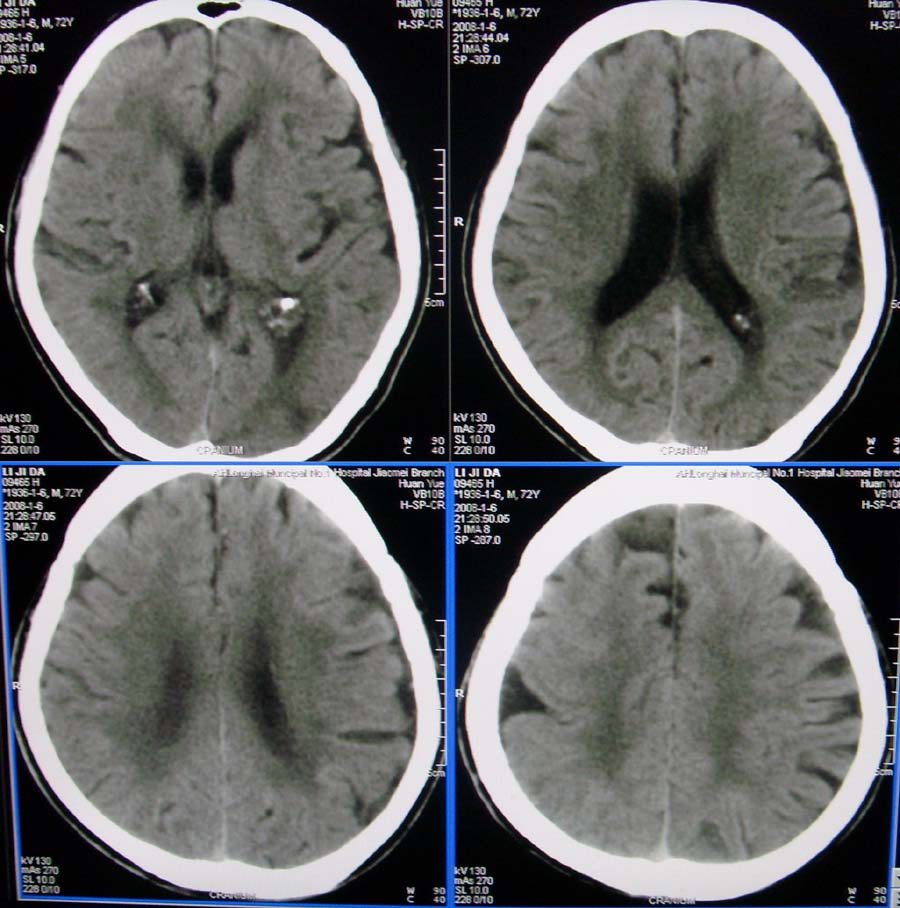

以下是引用随光逐影在2008-1-10 16:22:00的发言:[br]左侧外侧裂池内侧见一圆形等密度影,密度均匀,边界清晰,周围无水肿,位于左侧大脑中动脉走行区。考虑为:动脉瘤。建议:行进一步检查明确诊断。